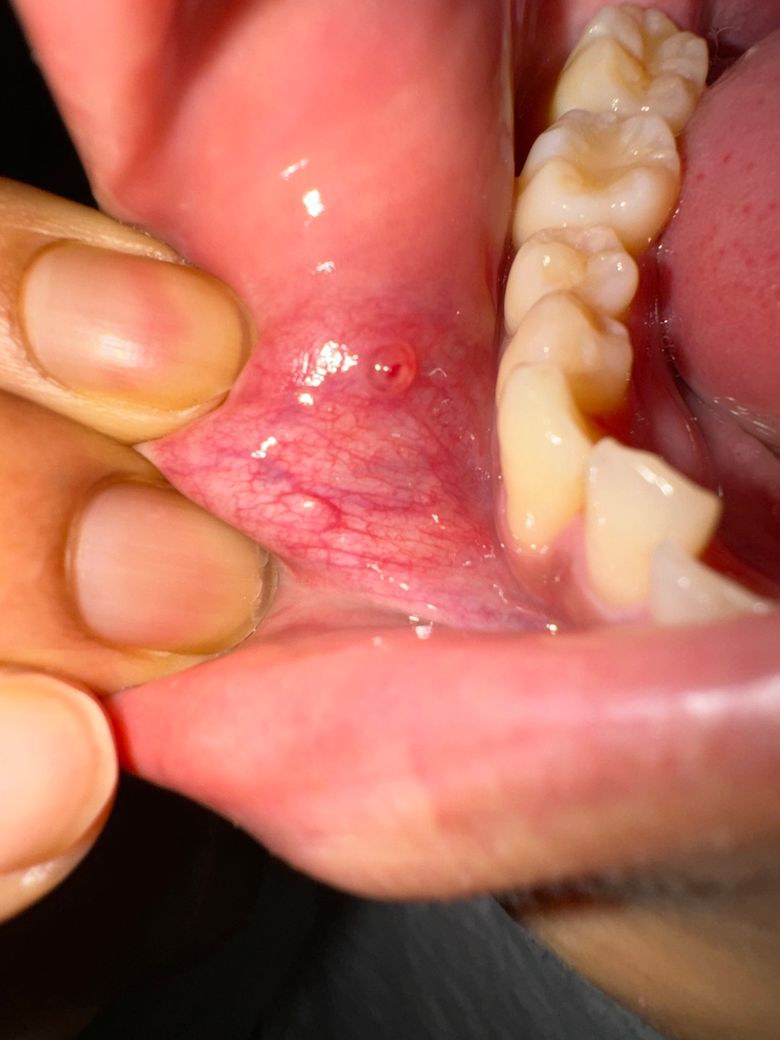

3주정도 되어가는데 입 안에 구내염인지 물집인지 뭔가가 안사라져요. 연휴라 병원을 갈 수도 없어서 질문드립니다. 사진 처음 두개는 2주전찍은거고 세네번째는 오늘 알보칠 바르고 3시간 후 찍은겁니다. 알보칠 발라도 아프지도않고 페리덱스, 페리톡겔 발라도 안사라지네요. 좀 가라앉았다가 다시 물집잡히고 그래요. 왜 그런걸까요? 최근에 스트레스도 많이 받고 잠을 되게 많이 못잤는데 영향이 있을까요?

사진에 보이는건 간단한 낭종으로 제거가 안되면 치과에 가셔서 마취후에 절제를 하거나 레이저로 제거를 하셔야됩니다.

사진으로 봤을 경우에는 점액종으로 보입니다. 점액종은 구강 점막의 과도한 힘이 가해졌을 경우 전망 내부에 조직액이 차면서 생기게 됩니다. 치아에 가해지는 힘을 줄여주시고 음식을 너무 강하게 먹지 않는 것이 좋습니다.

점액종은 대부분 시간이 지나면서 자연스럽게 없어지게 되며 치과에서 간단하게 제거할 수 있습니다. 자세한 확인을 위해서 치과에서 진료를 받아보는 것을 권유 드립니다.

현재 사진상 구내염이 있는 것으로 보이며, 최근에 스트레스도 많이 받고 잠을 되게 많이 못자서 해당부위가 회복이 되지 않을 가능성이 높습니다. 충분한 휴식과 비타민비군과 같은 영양소 섭취를 충분히 하길 권하며, 헥사메딘 소독용 가글액으로 가글하여 관리하여 주길 권합니다.